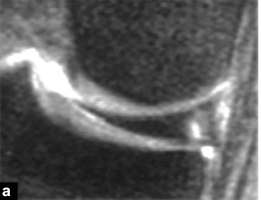

Elles se traduisent par un décalage de 5 mm du ménisque supérieur par rapport au bord postérieur du plateau tibial sur les clichés sagittaux (Fig. 11), ou une insertion liquidienne entre la base du ménisque et le plan de la capsule articulaire.

Figure 11 Décollement de la corne postérieure du ménisque.Vue sagittale de la densité de protons.Le ménisque séparé est déplacé vers l'avant.Il existe une large zone d'hypersignal (*) entre la base du ménisque et la capsule postérieure (flèche).

Ceci est le résultat d'une blessure violente et est dû à une rupture du ligament ménisco-tibial et à un décollement de la partie médiale du ménisque.En IRM, le ménisque séparé est complètement entouré de liquide et semble 'flotter' sur le plateau tibial (Figure 12).

Figure 12 Ménisque flottant.Vue frontale de la densité de protons avec saturation des graisses.Le ménisque séparé est entouré de liquide, notamment entre sa face inférieure et le plateau tibial (flèche).